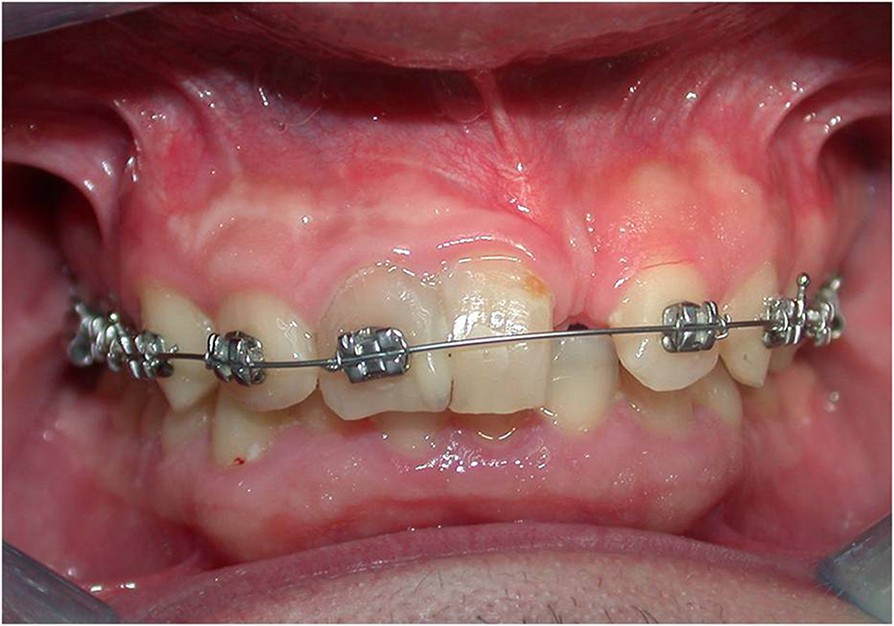

Figure 5 from Orthodontic treatment of fused and geminated central Fused Incisors this paper summarizes the treatment methods for fused teeth and classifies the management schemes according to. intraoral examination revealed that a permanent maxillary left lateral incisor was fused with a supernumerary tooth. primary fused teeth (pft) are more frequently observed in primary than in permanent dentition. The fused tooth had a broad. The main management of this. Fused Incisors.

Figure 3 from Orthodontic treatment of fused and geminated central Fused Incisors The main management of this clinical condition is. this paper summarizes the treatment methods for fused teeth and classifies the management schemes according to. primary fused teeth (pft) are more frequently observed in primary than in permanent dentition. intraoral examination revealed that a permanent maxillary left lateral incisor was fused with a supernumerary tooth. the data. Fused Incisors.

Figure 1 from Orthodontic treatment of fused and geminated central Fused Incisors the data disclosed the occurrence of double teeth in mandibular incisors. The fused tooth had a broad. fusion is a developmental anomaly defined as the union of two adjacent tooth germs at the dentin level. this paper summarizes the treatment methods for fused teeth and classifies the management schemes according to. this report discusses two cases. Fused Incisors.